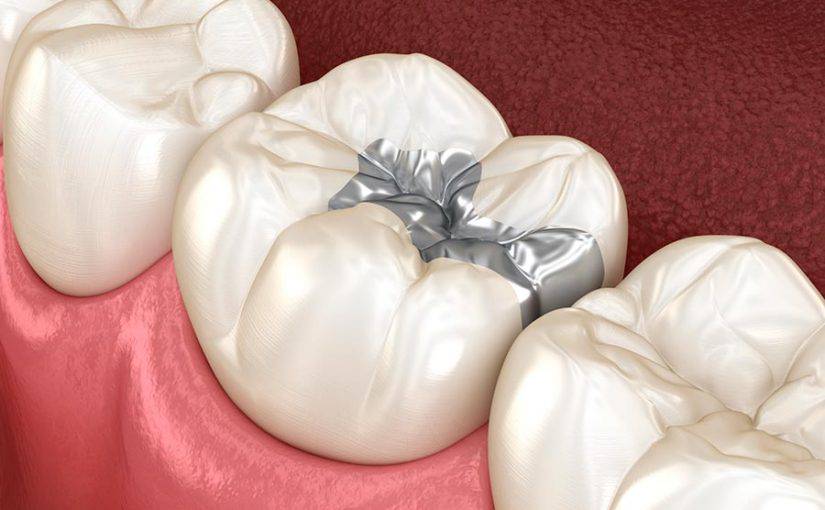

Las Amalgamas son un material de restauración utilizado para rellenar cavidades dentales causadas por Caries. Están compuestas por una mezcla de aleaciones de mercurio combinadas con uno o más metales como plata, estaño, cobre y zinc.

- Colocación de la Amalgama: La Amalgama se coloca en la cavidad preparada en capas. Cada capa se compacta para garantizar que la Amalgama llene por completo la cavidad y se adhiera al diente.

- Modelado y ajuste: Se da forma a la Amalgama para que se adapte a la anatomía natural del diente y a la oclusión. Esto puede implicar eliminar el exceso de empaste y dar forma a la superficie para que coincida con la mordida del paciente.